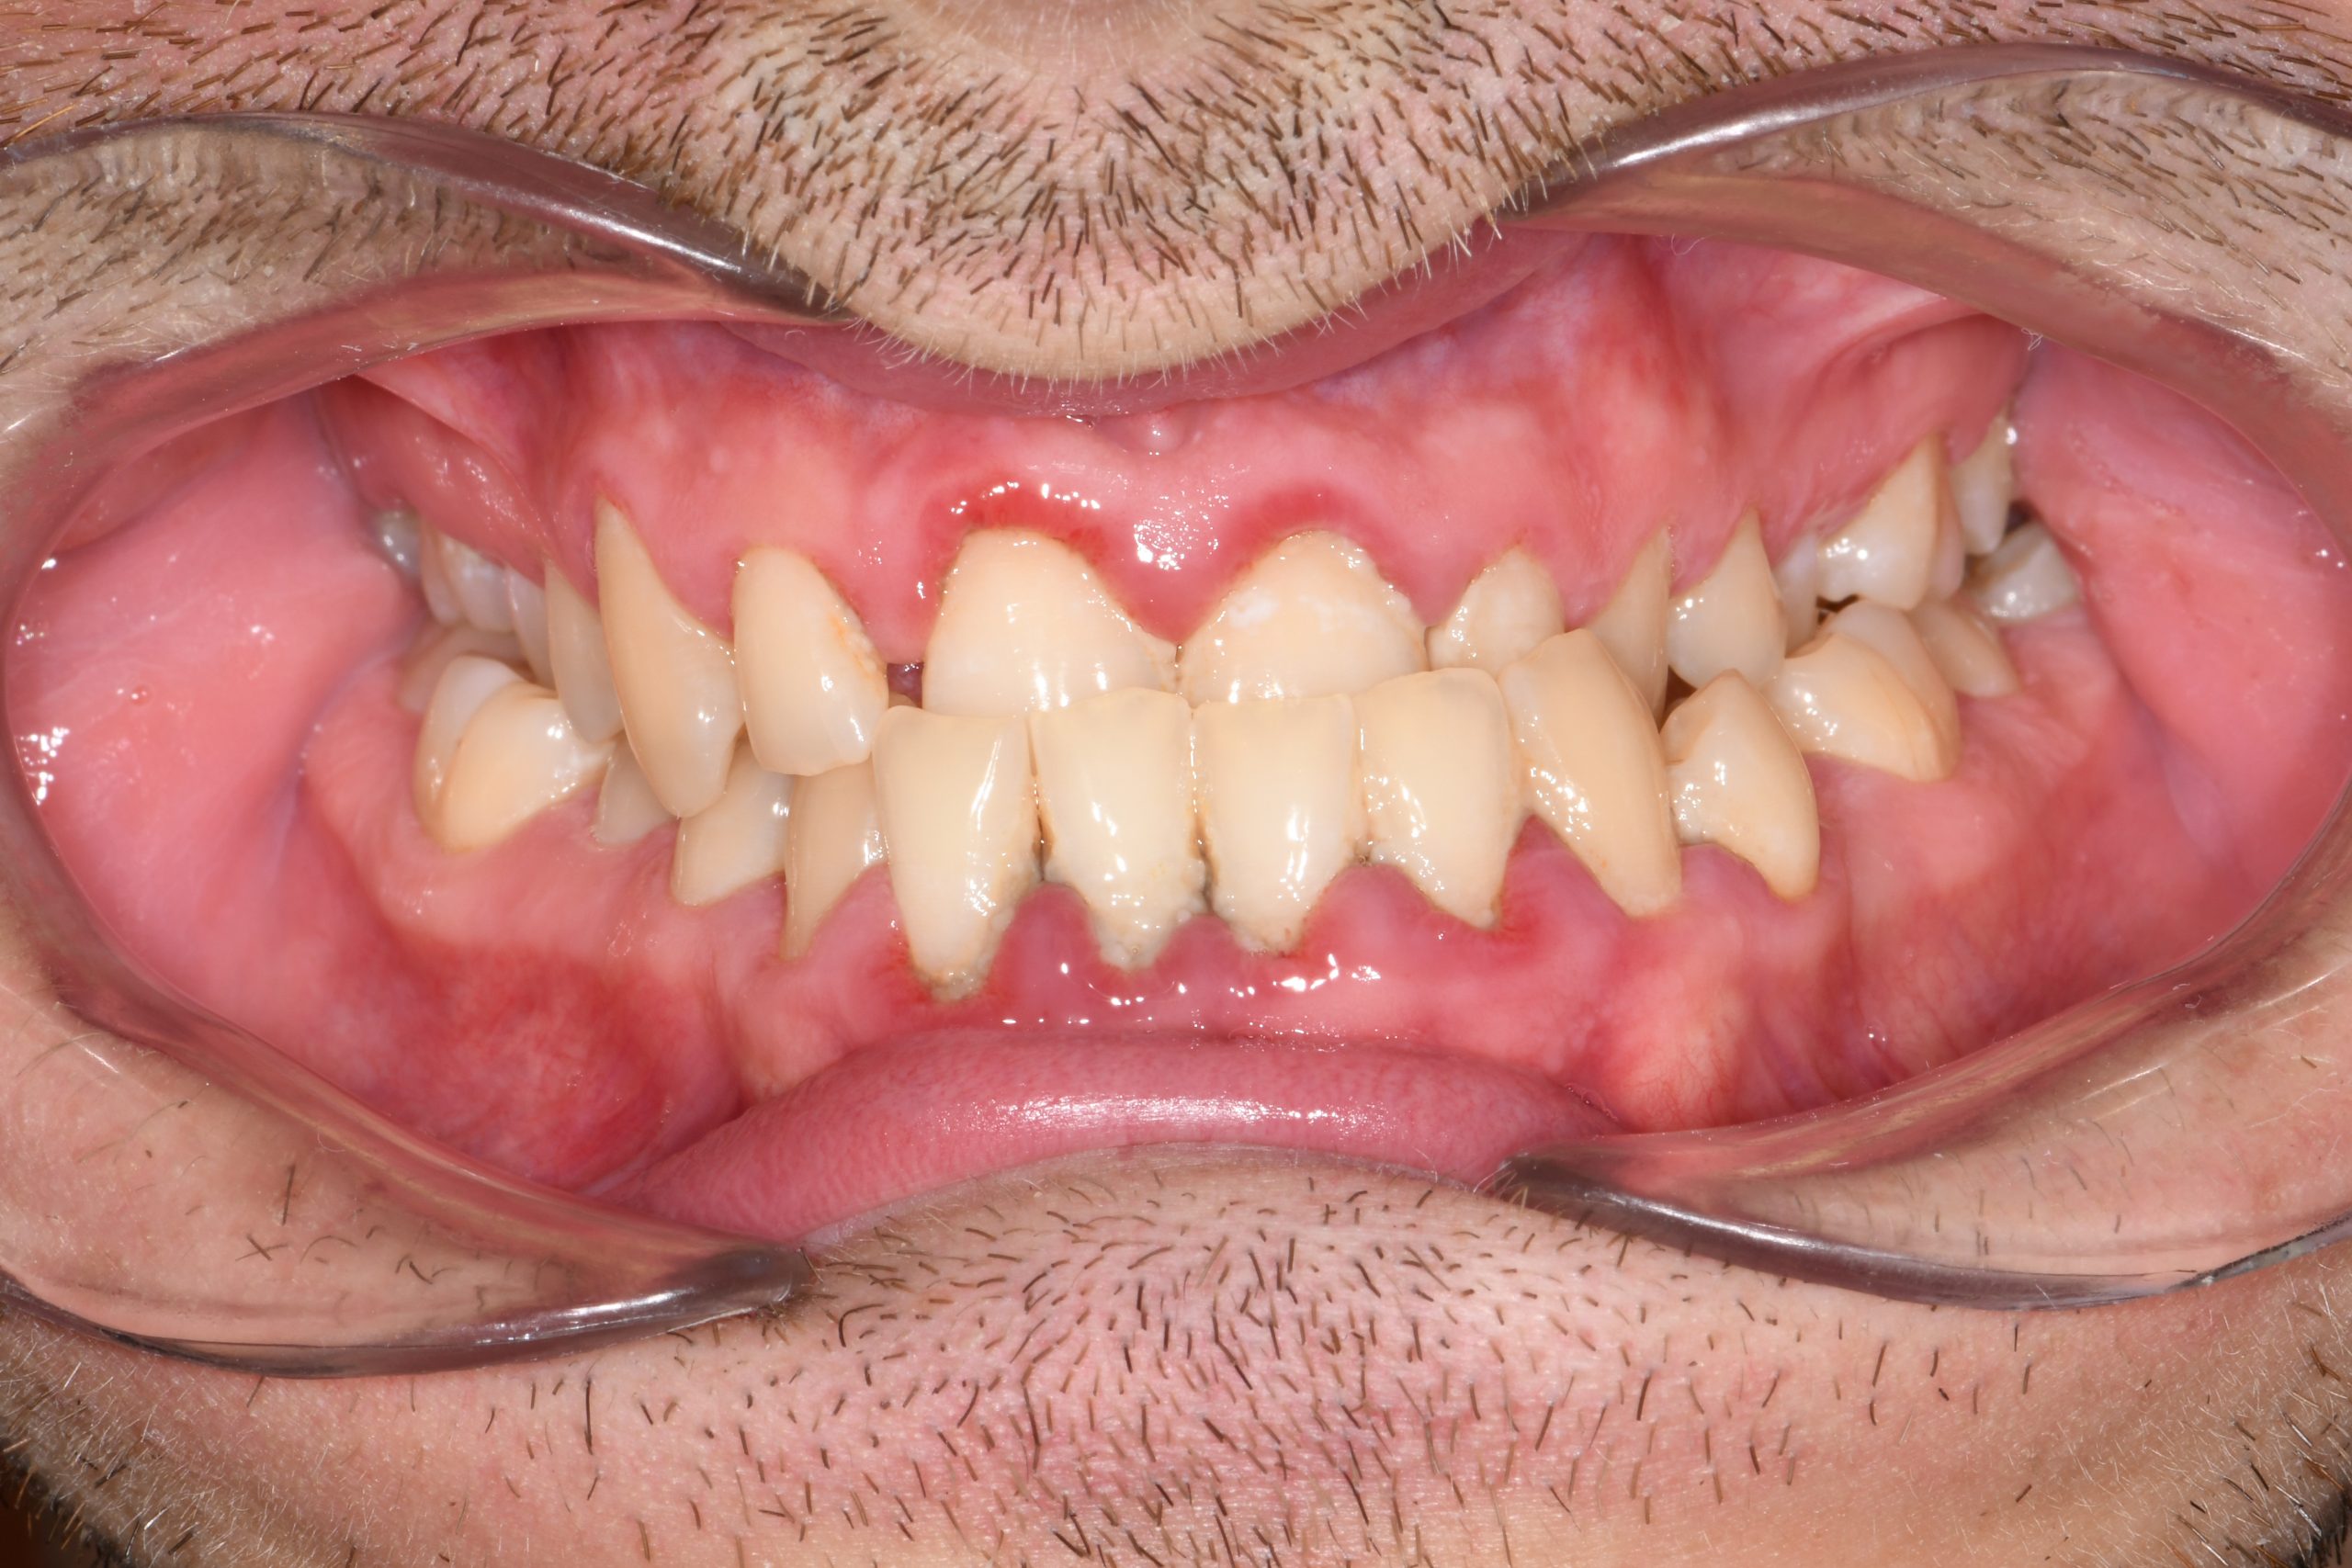

Az elmúlt évekből rengeteg szakmai referenciát tudnánk bemutatni, amelyek különböző fogszabályozási problémákat oldottak meg. Válogatva a több száz esetből, ezen az oldalon olyan képeket, információkat igyekeztünk bemutatni, amelyeknek a segítségével a jövőbeni pácienseinknek azt tudjuk üzenni: A Te fogsorod is lehet gyönyörű!

(Képeket a Pácienseink külön írásos beleegyezésével mutatjuk be!)